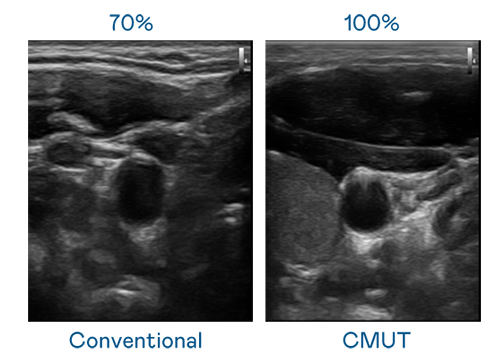

CMUT 技术是一种用电容式微机电元件来产生超音波讯号的技术。与传统 PZT 压电式技术相比,CMUT 频宽增加 30%,更宽频的超音波讯号让影像解析度大幅提升,是实现高影像品质医疗超音波扫描、促进精准医疗发展的关键技术。

超音波影像的解析度高低,首先取决于探头能发出的讯号频宽。304am永利 CMUT 可提供高清晰的超音波讯号,提供高频宽、高灵敏度、影像纹理细节更高的超音波影像,协助医护人员缩短影像判读时间及利用精准的医疗影像进行诊断。